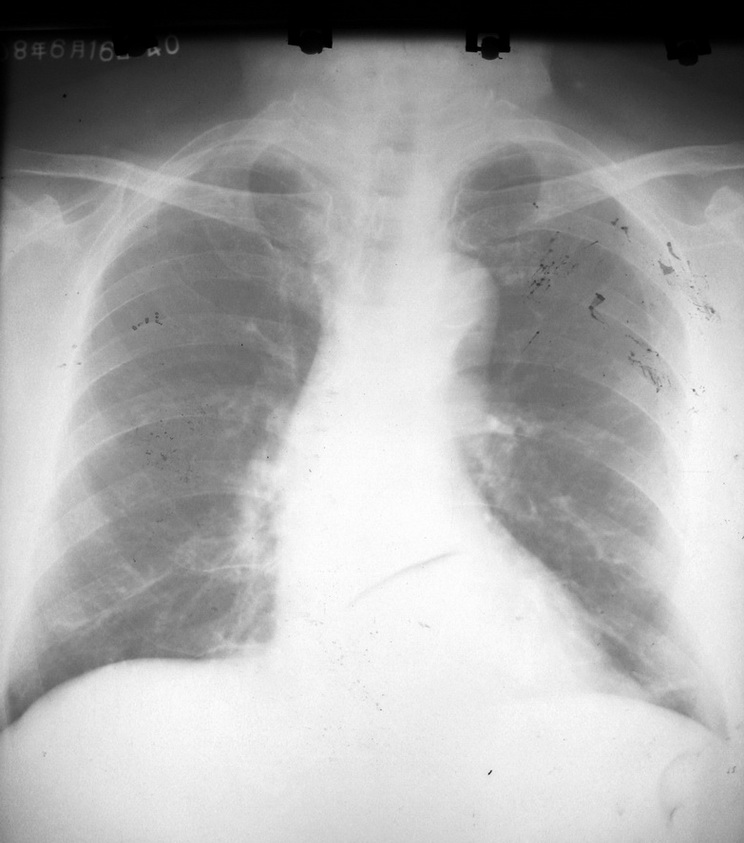

标题: X4404:男,65岁。体检 [打印本页]

标题: X4404:男,65岁。体检

左下肺局限性纤维化,余未见明显异常。

双肺纹理增强,左下肺横行致密条状影,考虑盘状不张。主动脉迂曲延长。

考虑:1、主动脉硬化;

2、左下肺纤维灶。

左侧胸膜肥厚可能性大.

建议:ct扫描.除外其他病变之可能.

左下胸膜肥厚。建议:结合临床必要时ct扫描。

1、两下肺野纤维病灶

2、主动脉弓粥样硬化

3、左侧胸壁胸膜增厚不排除(亦可能为体位关节所致)

支持 双肺纹理增强,左下肺横行致密条状影,考虑盘状不张。主动脉迂曲延长。